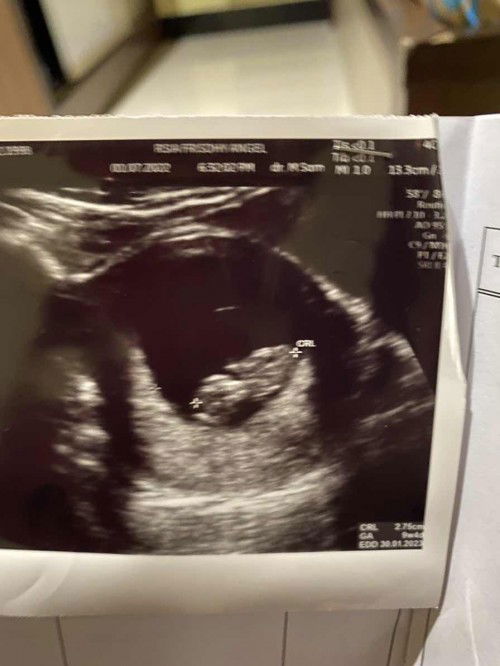

Kehamilan 9week

Permisi dokter,bidan, para bnd saya mau tanya di kehamilan sya 9week4d dok bilang tangan kaki belum tumbuh atau terlihat apa itu wajar/ normal mohon bantuan nya terimakasi